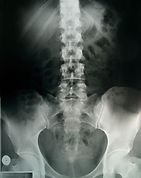

Infrared Thermography in Medical Diagnosis

Scoping Review of Infrared Thermography in Medical Diagnosis, Screening and Disease Monitoring.